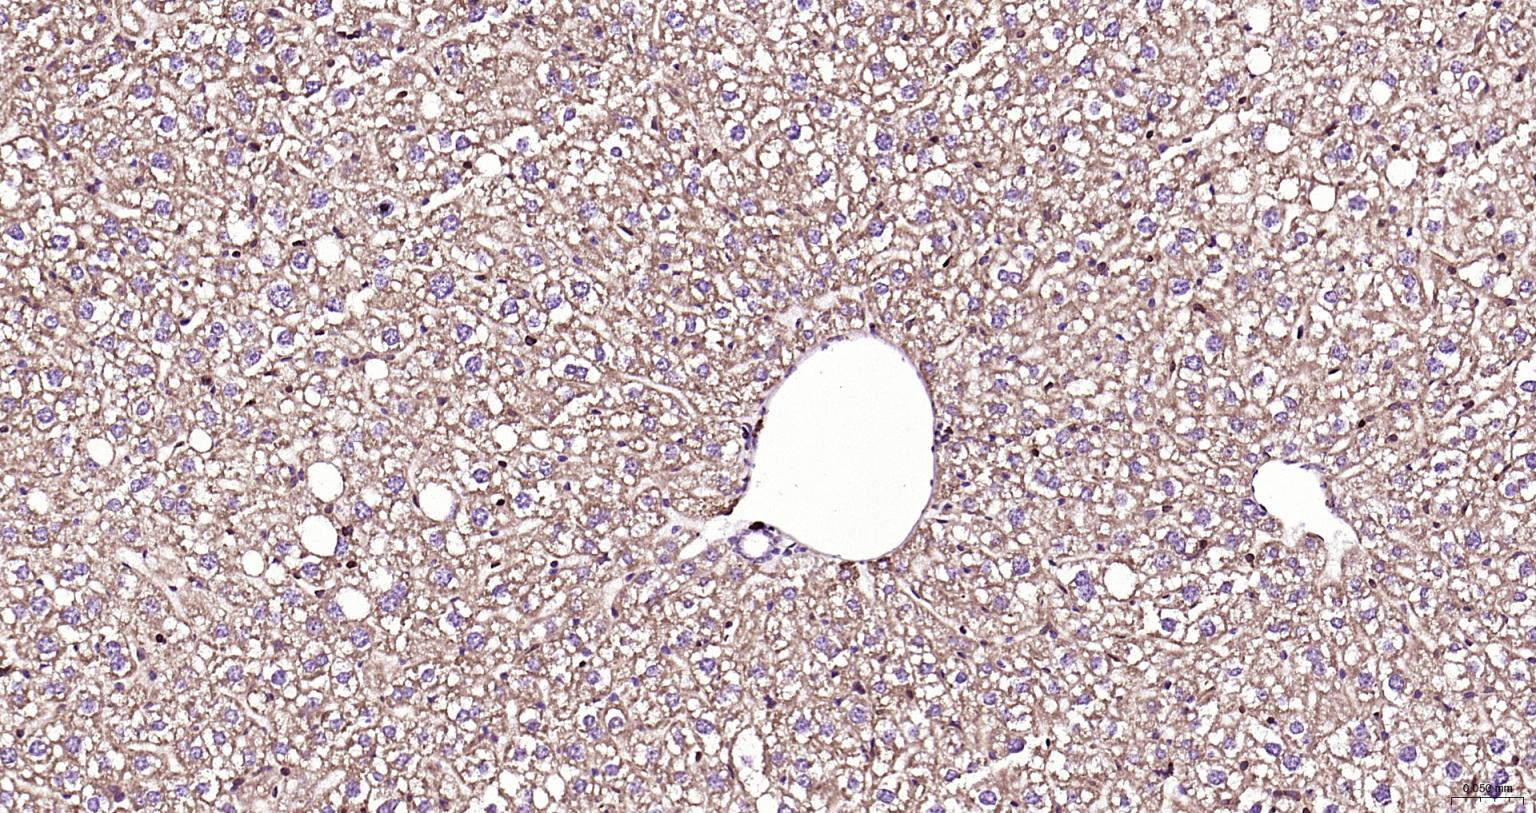

Tissue/cell: mouse lymphoma tissue; 4% Paraformaldehyde-fixed and paraffin-embedded; Antigen retrieval: citrate buffer ( 0.01M, pH 6.0 ), Boiling bathing for 15min; Block endogenous peroxidase by 3% Hydrogen peroxide for 30min; Blocking buffer (normal goat serum,C-0005) at 37℃ for 20 min; Incubation: Anti-Smad3 Polyclonal Antibody, Unconjugated(bs-3484R) 1:200, overnight at 4°C, followed by conjugation to the secondary antibody(SP-0023) and DAB(C-0010) staining